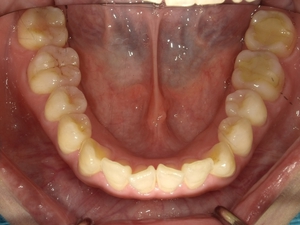

ガタガタとした歯並びや八重歯(叢生)CASE7